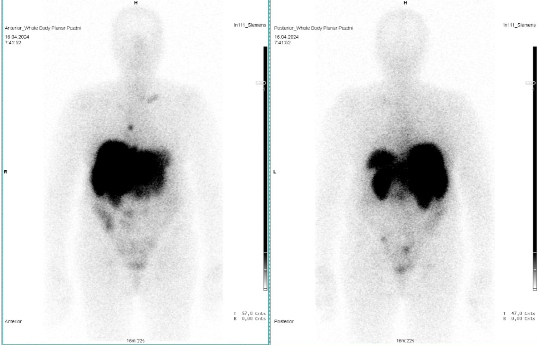

Scintigrafie Octreoscanem

I. v. jsme aplikovali 190 MBq analogu somatostatinu značeného 111In

(přípravek OctreoScan firmy Curium Netherlands B.V.) a provedli pomocí hybridní tomografické scintilační kamery Siemens Symbia Pro.specta X3 opatřené kolimátory pro střední energie planární celotělovou scintigrafii a cílenou tomografickou scintigrafii (SPECT) břicha a pánve kombinovanou s CT.

/ Obr. č. 3: Fúze SPECT/CT 4 hod. po aplikaci OctreoScanu. /

/ Obr. č. 4: Fúze SPECT/CT 4 hod. po aplikaci OctreoScanu. /

/ Obr. č. 5: Fúze SPECT/CT 4 hod. po aplikaci OctreoScanu. /

/ Obr. č. 6: Celotělová scintigrafie v přední a zadní projekci 24 hod. po aplikaci OctreoScanu.

/

Popis: pozorujeme patologická ložiska zvýšené depozice radiofarmaka-nově nekontrastně ve více LU v levém nadklíčku, v jedné parasternální LU vpravo (úroveň Th6) vel. 10 mm, v LU v dolním mediastinu prekardiálně cca 17 mm, tomograficky zachycena chabě zvýšená akumulace RF v Th páteři v úrovni obratlového těla Th7 a Th8 (v ldCT bez patologického korelátu, nově však v ldCT obraze zjištěna v. s. lýza pravého postranního výběžku obratle Th8), v levém jaterním laloku - S4b, v pravém jaterním laloku - S5 a S6, v LU paraaortálně v úrovni L2/3 15,5 mm - dnes okrsek nápadnější, chabě v levé kosti kyčelní dorsálně při SIS - částečná regrese od min. vyšetření.

Nález svědčí pro přítomnost vícečetných patologických ložisek zvýšené denzity somatostatinových receptorů ve výše uvedených lokalizacích. Ve srovnání s posledním vyšetřením jsou detekována nová ložiska v levém nadklíčku a mediastinu, susp. diskrétní nález i v Th páteři (obratel Th7 a Th8) se zachycenou lýzou postranního výběžku obratle Th8 vpravo v CT obraze, částečná regrese okrsku v levé kosti kyčelní oproti minulému vyšetření.

Závěr:

U nyní 70leté ženy s neuroendokrinním tumorem nejasného primárního zdroje prokazujeme progresi nálezu oproti vyšetření před 22 měsíci.